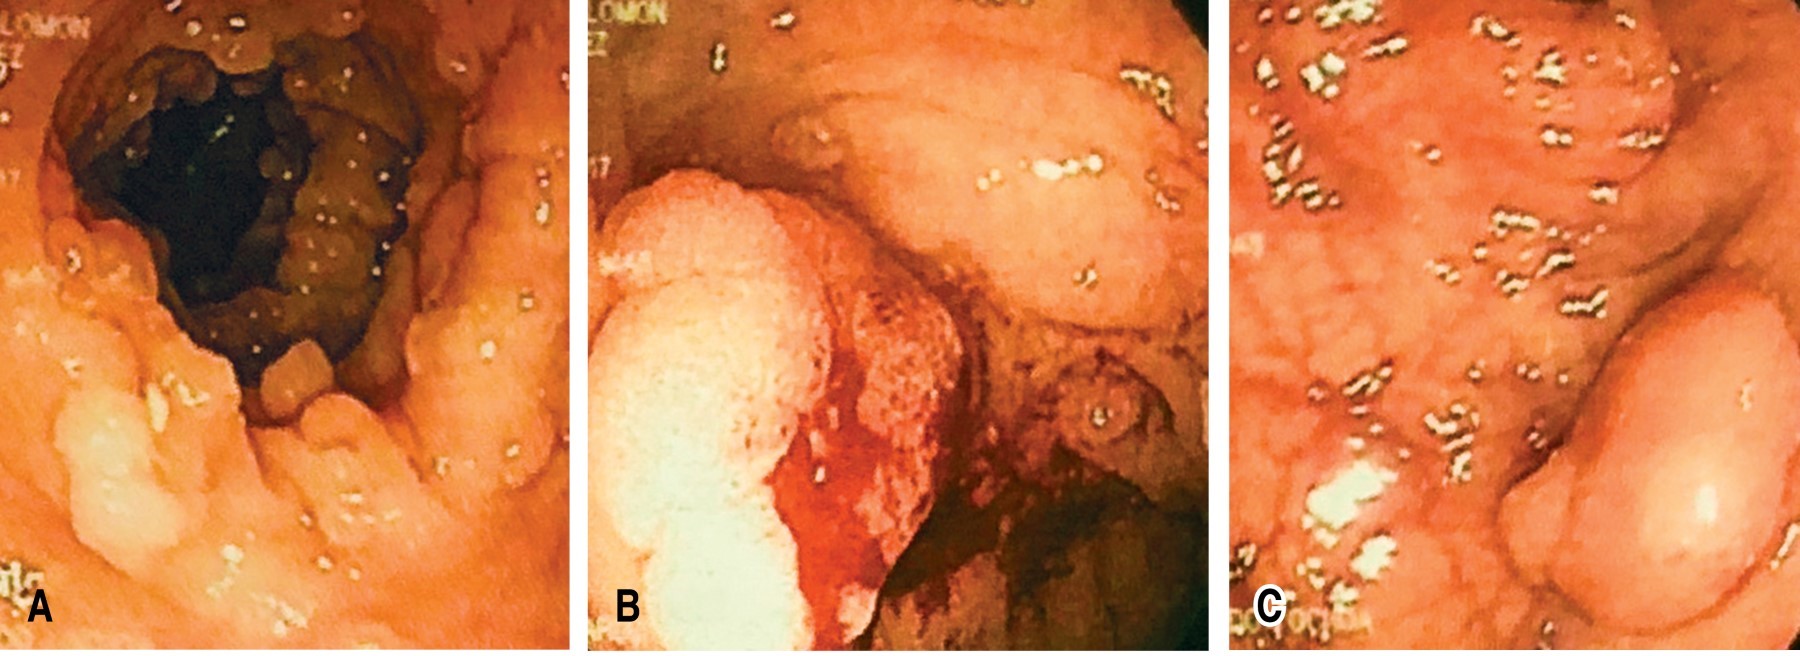

The patient is a 56-year-old man under medical treatment for long-standing arterial hypertension and ischemic heart disease treated with coronary stent placement two years ago, with a hereditary family history of colon cancer in two first-degree relatives under 50 years of age. He came for external evaluation due to a history of three months of evolution with lower gastrointestinal tract bleeding (LGITB) accompanied by anemic syndrome; a colonoscopy was performed, and multiple polyposis was observed (more than 200 polyps), with neoplastic lesions in the sigmoid colon and transverse colon (Figure 1). No abnormal skin or bone lesions were found, nor was the presence of hypertrophy of the retinal epithelium pigment identified.

The study was complemented with an endoscopy of the upper gastrointestinal tract showing a diffuse micronodular surface in the upper portion of the body of the stomach, without duodenal polyps (Figure 2), and a thoracoabdominal computerized tomography (CT) scab with IV contrast revealed a transverse colon tumor with peri-colonic fat infiltration conditioning partial obstruction, as well as the presence of para-aortic lymphadenopathies (Figure 3). Laboratory studies showed hemoglobin: 9.0 g/dl, total protein: 5.8 g/dl, albumin: 3.0 g/dl and carcinoembryonic antigen: 131 ng/ml.

Figure 2